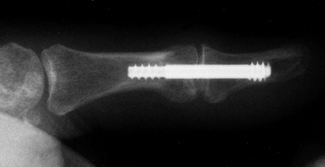

formation (8,111,194,226). Fracture malunion is a common and potentially avoidable complication (Fig. 67.2).

![]() |

Figure 67.2.

Malunited fractures of the radius and ulna in a brain-injured patient. Because the patient was not expected to survive, the fractures were not treated initially. |